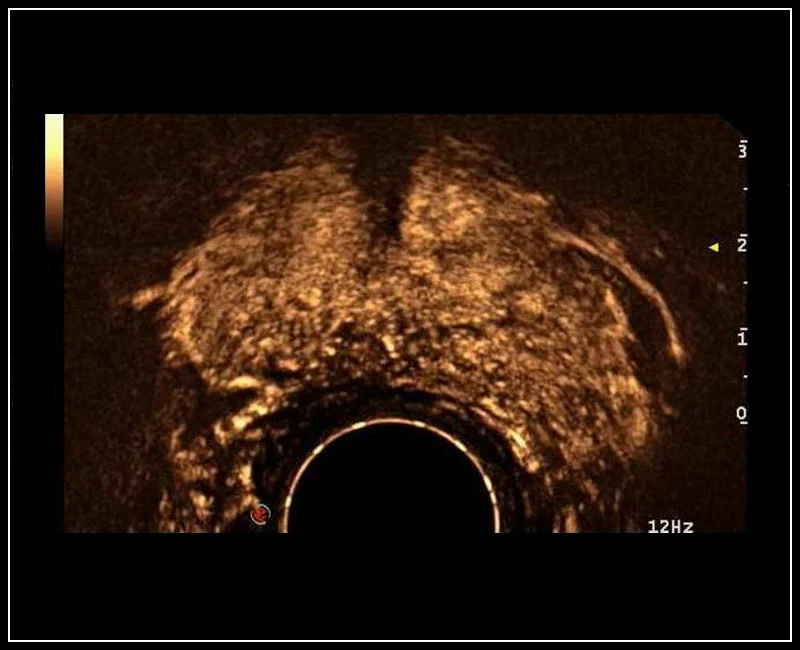

MyLab™9 Platform - Prostate contrast enhanced imaging (CnTI™)

MyLab™9 Platform - Prostate contrast enhanced imaging (CnTI™)